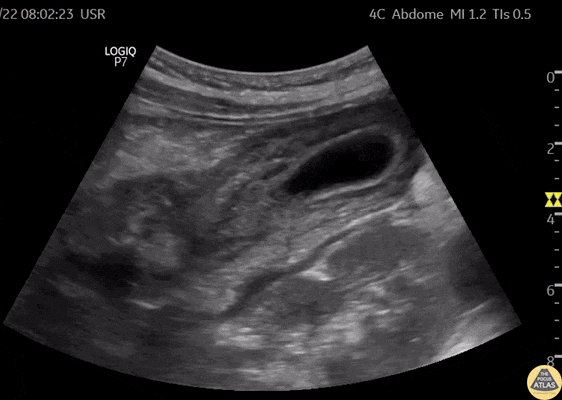

Biliary